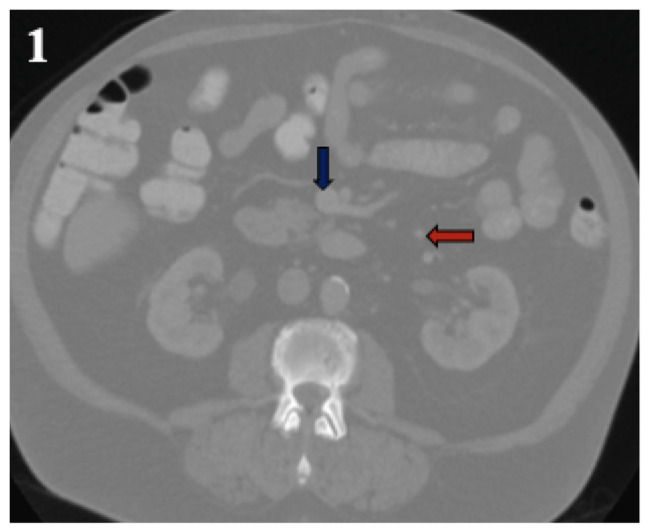

Sclerosing mesenteritis (SM) is a rare idiopathic fibroinflammatory disorder of the bowel mesentery adipose tissue. While the use of rituximab has been documented in IgG4-related SM, its effectiveness in idiopathic, IgG4-unrelated SM remains unknown. We present a case of idiopathic SM successfully managed with rituximab, suggesting that this treatment may be an option for patients who either have contraindications to or have not responded to current first-line therapies.